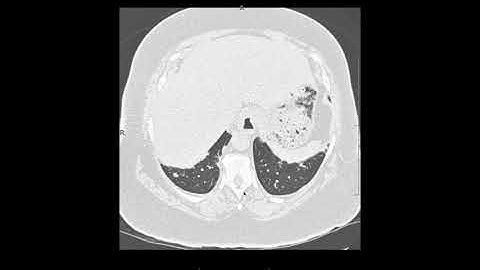

NSIP Explained